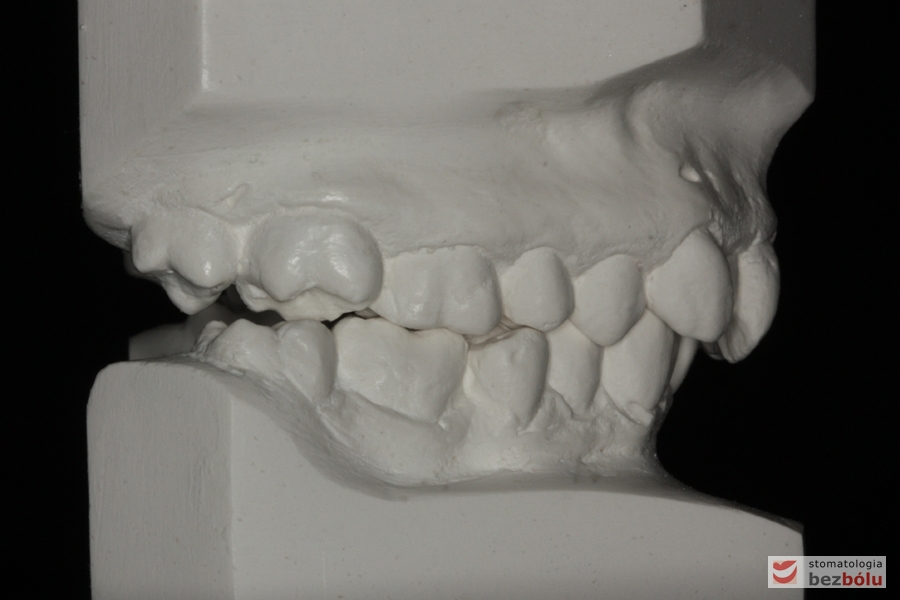

Pacjentka lat 26 zgłosiła się do gabinetu celem korekcji uśmiechu. Głównym zmartwieniem były problemy estetyczne, które znacznie wpływały na jakość życia pacjentki. Wykonano leczenie zachowawcze zębów oraz analizę cefalometryczną i analizę modeli diagnostycznych. Zaplanowano leczenie aktywne aparatem DAMON dla szczęki i żuchwy, które trwało 2 lata. Po fazie leczenia aktywnego rozpoczęto leczenie retencyjne z użyciem szyny tłoczonej dla szczęki i retainera stałego dla żuchwy.